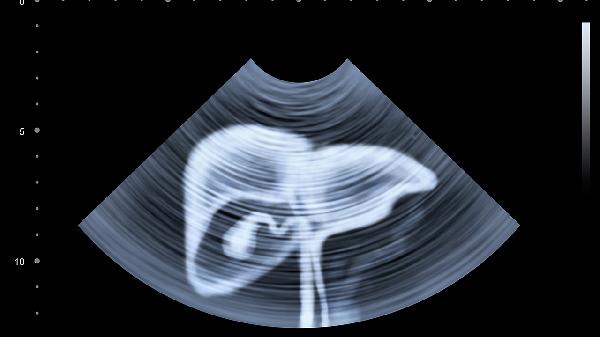

肝脾肿大可致腹部轮廓异常,叩诊呈浊音。腹水形成时可见脐部突出或移动性浊音,腹围短期内增加超过2厘米需重视。先天性肝纤维化、糖原累积症等遗传代谢病常伴此体征。

发现上述症状建议完善肝功能检测ALT/AST值、凝血功能筛查及腹部超声。日常需保证足够热量摄入,选择中链脂肪酸配方奶粉更易吸收。避免使用对乙酰氨基酚等肝毒性药物,接种甲肝、乙肝疫苗可预防病毒性肝炎。母乳喂养母亲应戒酒并慎用中药制剂,定期监测宝宝生长发育曲线有助于早期发现异常。